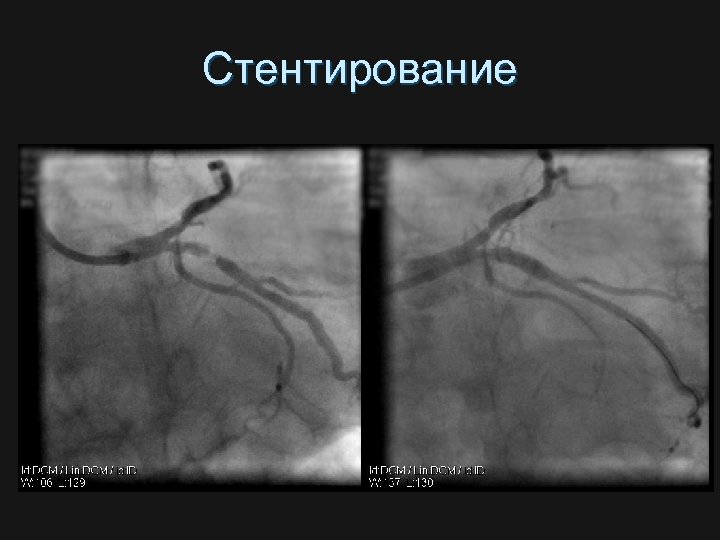

Стентирование

Этапы стентирования А В С